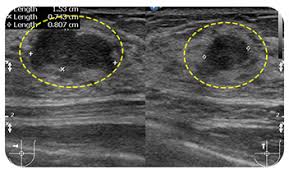

📷 맘모톰 수술 전후 사진

아래는 유방에 작은 혹을 맘모톰으로 제거한 후 절개흉터가 거의 보이지 않는 사례 사진입니다.